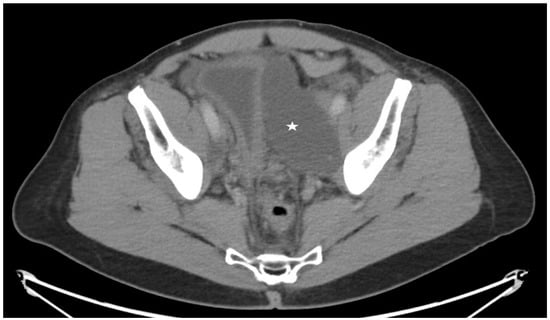

Figure 5. Axial cut from a Computed tomography of the pelvis for a 65-year-old patient with a left pelvic lymphocele (star) after prostatectomy and pelvic lymph node dissection.

Figure 6. Spot image from an intra-nodal lymphangiogram for the same patient in Figure 5 showing a 25-gauge needle within a left inguinal lymph node (arrow) and lipiodol within the lymphatic vessels (arrowhead). Lipiodol is seen leaking close to the indwelling pelvic lymphocele drain (circle) confirming the lymphatic leak.